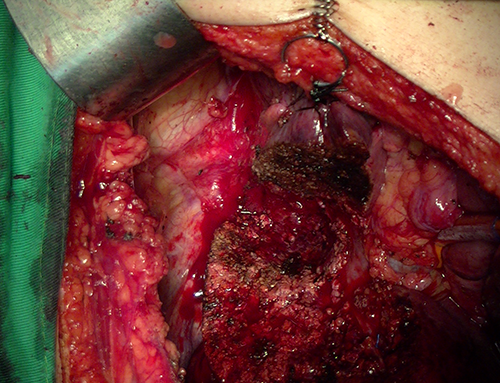

S8肝癌---改良肝中叶切除(3D打印)